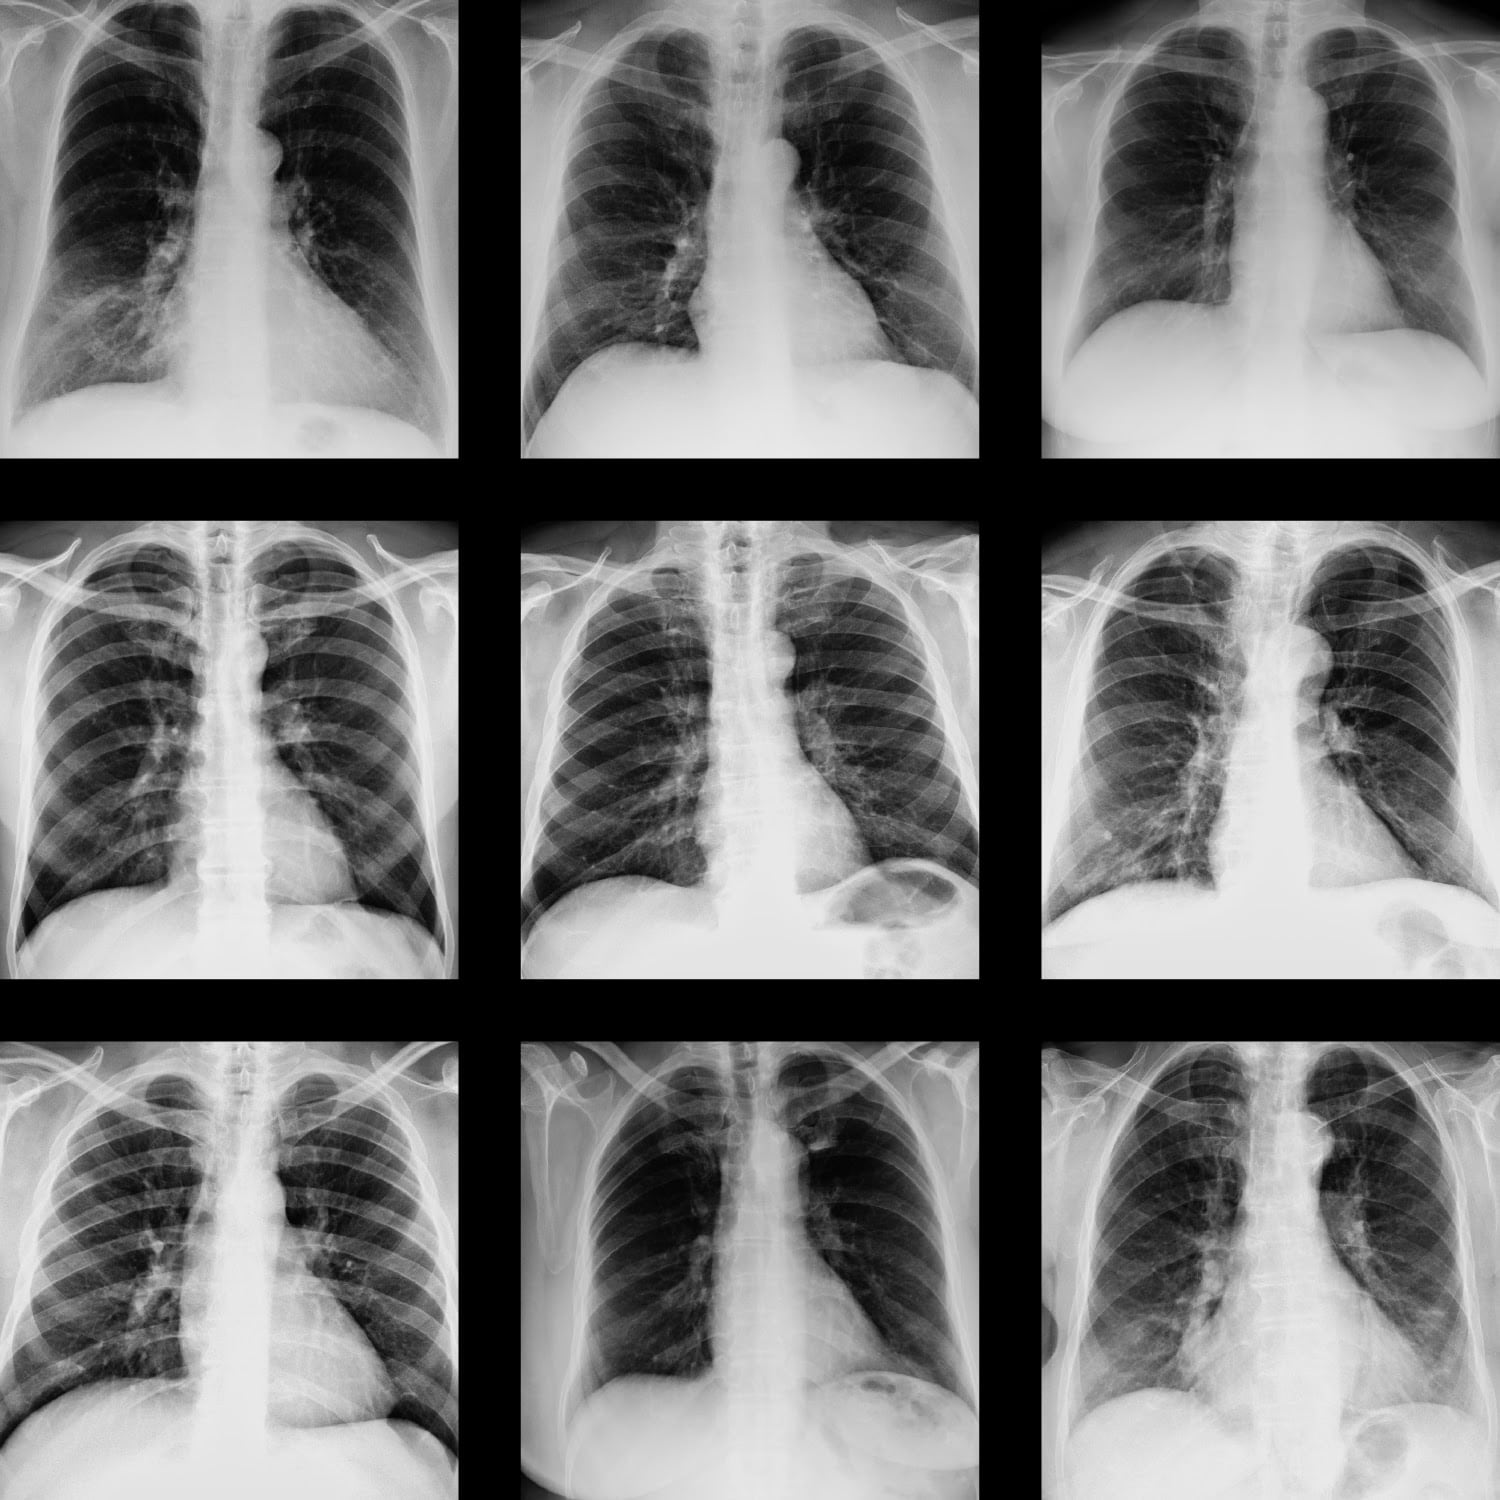

El grupo de investigadores y Saúl creen que las radiografías de pecho podrían ser de utilidad para determinar si una persona está infectada con la enfermedad COVID-19.

El diagnóstico podría realizarse asistido por computadora, utilizando técnicas avanzadas de inteligencia artificial, como el deep learning.

La tarea implica desarrollar un modelo de inteligencia artificial para estimar, a partir de imágenes de rayos X de pechos, daños por COVID-19.

“Nuestro objetivo es desarrollar un sistema de inteligencia artificial que ojalá mejore la sensibilidad de diagnóstico”, dice Saúl.

Los sistemas de deep learning típicamente trabajan con grandes bases de datos. Pero es difícil conseguir datos etiquetados del COVID, por el rápido avance de la pandemia.

La solución podría ser implementar algoritmos “semisupervisados”, con un 90% de acierto, que permite explotar datos no etiquetados.

El método sería de gran ayuda en centros médicos en comunidades alejadas, donde hay limitaciones para realizar pruebas de la COVID-19 y sí es posible mayor acceso a equipo de rayos X.

Desde estos centros se podría utilizar el sistema de inteligencia artificial de forma remota.